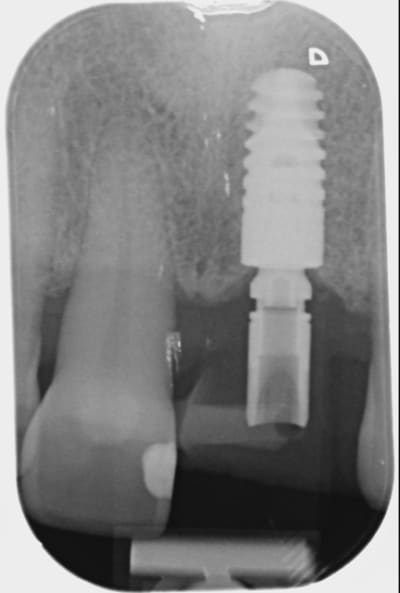

05/08/2014 à 20h20

Je ne sais pas si tu as réellement ingressé car quad je regarde ta radio du départ et celle que tu viens de mettre, ton apex arrive pratiquement au même niveau de spire, à savoir au niveau de la troisième spire en partant de l'apex de l'implant. Il y a quelque chose qui m'échappe.

Img 1744 z0evts - Eugenol